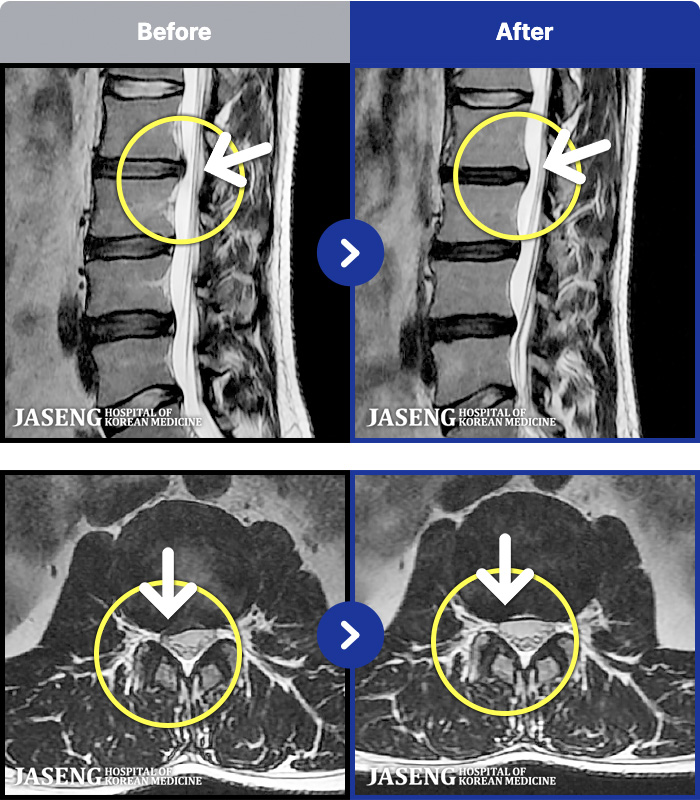

MRI ġ

MRI ũ ʸ Ȯϼ.